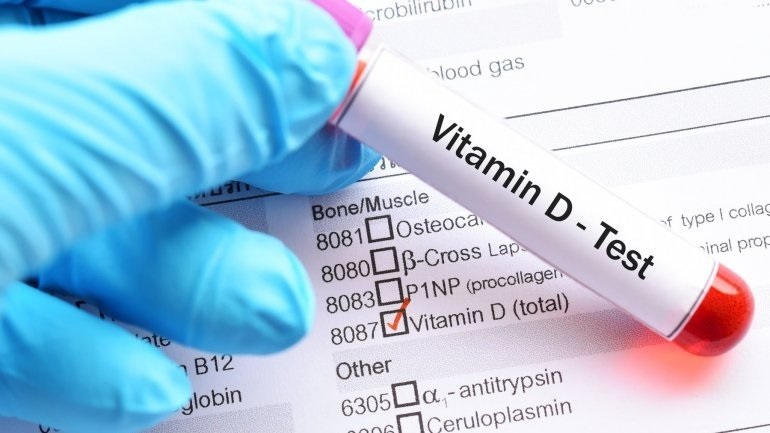

Μελέτη βρήκε ότι λήψη υψηλών δόσεων βιταμίνης D δεν επηρέασε τη συχνότητα εμφάνισης καρδιαγγειακών παθήσεων ή καρκίνου